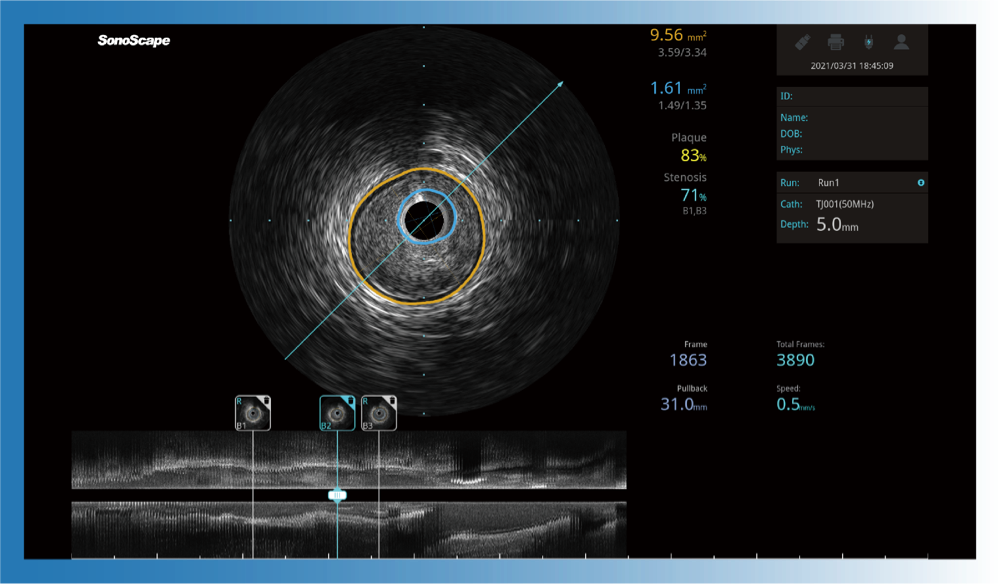

治疗前后两次测量录像对比

简化疗效评估

一键智能描迹,自动测量斑块负荷、面积狭窄率等指标,准确率高于90%